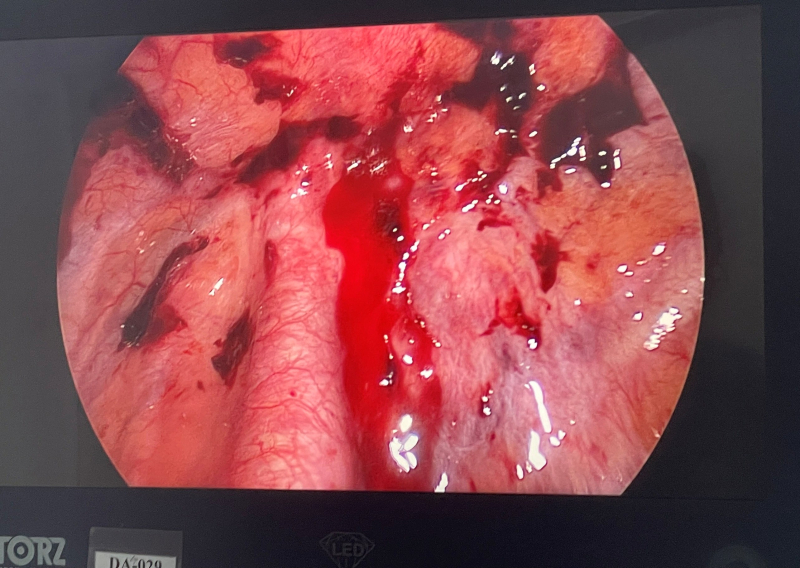

Hình ảnh máu đang chảy ra từ dây chằng đỉnh phổi.

Sau hơn 01 tiếng phẫu thuật, Bác sĩ CKI Hoàng Văn Quyết, Trưởng phòng Tổ chức cán bộ cùng Ekíp đã đã tiến hành Phẫu thuật nội soi lồng ngực cấp cứu, trong mổ hút được ~1000ml dịch máu lẫn máu cục trong khoang màng phổi, kiểm tra thấy có máu đang chảy ra từ dây chằng đỉnh phổi và từ thùy trên phổi trái do vỡ kén khí và đứt dây chằng. Bác sĩ đã tiến hành cầm máu điểm chảy máu, cắt và khâu lại kén khí vỡ, bơm rửa sạch và dẫn lưu khoang màng phổi. Hiện tại sau một ngày phẫu thuật, sức khỏe bệnh nhân đã ổn định.